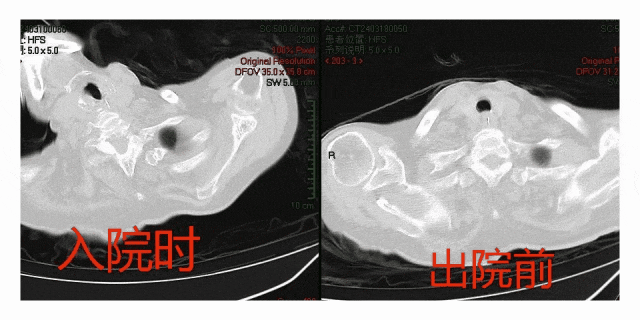

快、准、稳,气管镜下重症医生快速找到引起气管堵塞的部位,吸除了造成右上、右中肺堵塞的痰栓开通了气道,患者氧饱度的改善也是立竿见影。随后在有效的个体化治疗和护理团队的精心照料下,患者病情日渐好转,住院1周时复查胸部CT,阻塞的病灶完全消除(见图2),患者已于近期康复出院。